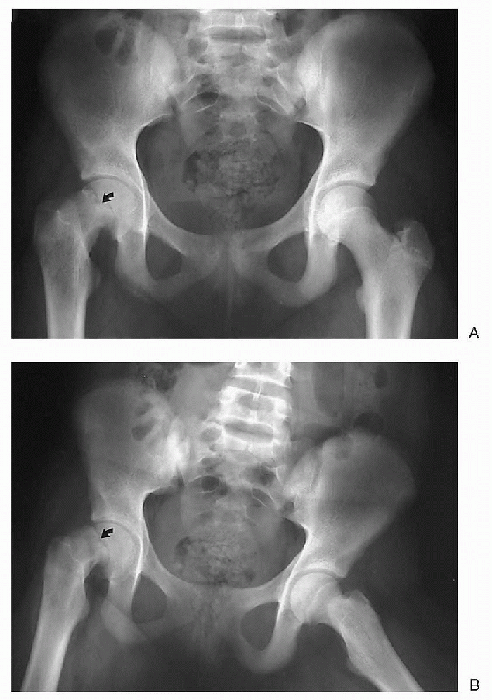

Figure 32-11 Slipped capital femoral epiphysis. (A) Frontal view. (B)

Frog-leg lateral view. The right femoral head has slipped medially on the frontal view and posteriorly on the frog-leg lateral view (arrows). A frog-leg lateral is a frontal view of the pelvis but a lateral view of the femur. |

The diagnostic imaging workup of slipped

capital femoral epiphysis (SCFE) consists of radiographic evaluation of

the pelvis in the frontal neutral and frog-leg lateral projections.-

□ The frog-leg lateral radiograph is more sensitive than the neutral radiograph in the detection of an SCFE (Fig. 32-11).

Radiographs are used to follow these patients after surgical pinning.

-

□ Alterations in pin position,

chondrolysis, or osteonecrosis are complications to be excluded on

follow-up radiographic evaluation.

CT can also be used to evaluate a SCFE, although generally plain films suffice.